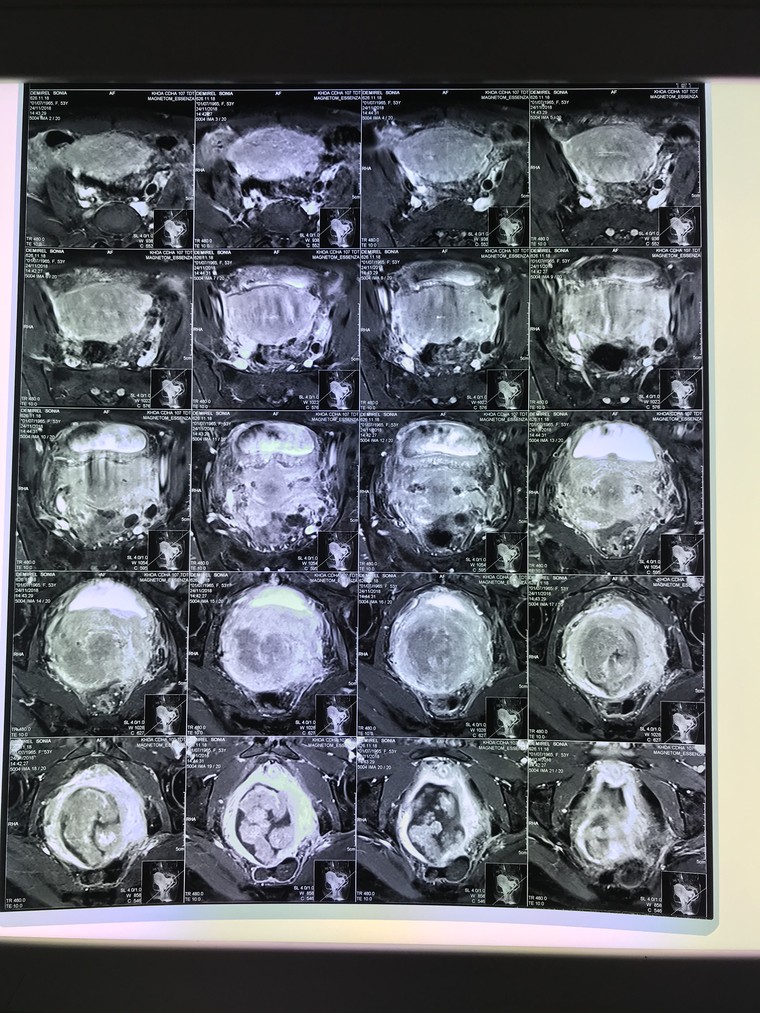

Hình ảnh khối u xâm lấn trên bệnh nhân S. Ảnh: VGP/Trần Hà

Mới đây, khoa Hồi sức cấp cứu, Bệnh viện K đã tiếp nhận trường hợp nữ bệnh nhân S. (54 tuổi), chẩn đoán ung thư cổ tử cung, nhập viện trong tình trạng ra máu âm đạo, chóng mặt, buồn nôn, da xanh niêm mạc nhợt, vô niệu.

Xét nghiệm cho thấy, bệnh nhân bị suy thận cấp do khối ung thư cổ tử cung xâm lấn lan rộng. Các bác sĩ đã truyền máu, lọc máu, cấp cứu tích cực cho bệnh nhân. Bệnh nhân được chẩn đoán bị suy thận cấp và mắc ung thư cổ tử cung giai đoạn IV, sẽ tiếp tục được theo dõi và điều trị theo phác đồ.